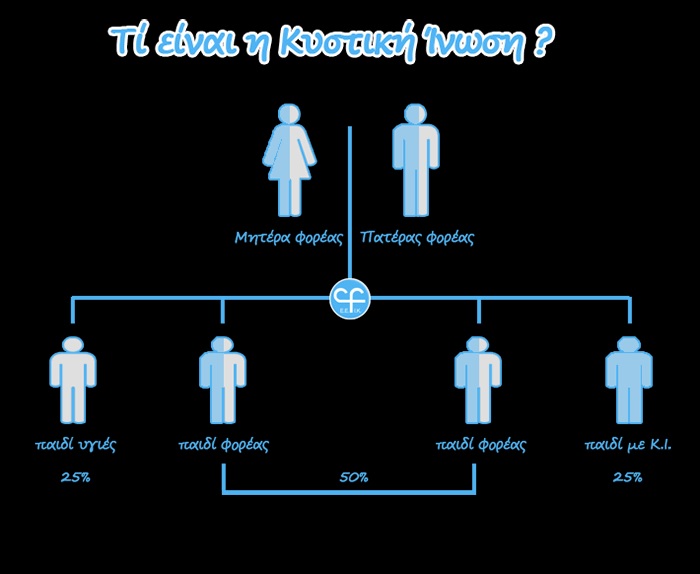

Πώς κληρονομείται

Πρόκειται για μια γενετική διαταραχή –συνεπώς μη μεταδοτική– που οι ασθενείς φέρουν από τη γέννησή τους, έχοντας κληρονομήσει δύο παθολογικά γονίδια της Κυστικής Ίνωσης, ένα από τον κάθε γονέα τους. Τα άτομα που φέρουν ένα μόνο παθολογικό γονίδιο λέγονται φορείς του γονιδίου και θεωρούνται απολύτως υγιή. Για να γεννηθεί ένα παιδί με Κυστική Ίνωση πρέπει απαραίτητα και οι δύο γονείς του να είναι φορείς ή ασθενείς. Οι πιθανότητες εμφάνισης της νόσου για κάθε παιδί καθορίζονται από τον κανόνα του Mendel.

Παρακάτω αναφέρονται οι περιπτώσεις και οι πιθανότητες που υπάρχουν να είναι κάποιος πάσχων, φορέας ή να μην φέρει καθόλου το γονίδιο:

– Στη συνήθη περίπτωση δύο γονέων-φορέων, για κάθε παιδί υπάρχουν πιθανότητες 25% να πάσχει από τη νόσο, 50% να είναι φορέας και 25% να μην φέρει καν το γονίδιο.

– Από ένα γονέα πάσχων και ένα γονέα-φορέα, κάθε παιδί έχει πιθανότητες 50% να πάσχει από τη νόσο και 50% πιθανότητες να είναι φορέας.

– Από ένα γονέα που δεν φέρει καθόλου το γονίδιο και ένα γονέα-φορέα, δεν υπάρχει πιθανότητα γέννησης παιδιού που να πάσχει από την νόσο, αλλά κατά 50% κάθε παιδί είναι πιθανό να είναι φορέας.

– Από ένα γονέα που δεν φέρει καθόλου το γονίδιο και ένα γονέα-πάσχοντα, όλα τα παιδιά θα είναι φορείς.

– Τέλος, δύο γονείς που πάσχουν μπορούν να κάνουν μόνο παιδιά που θα νοσούν.